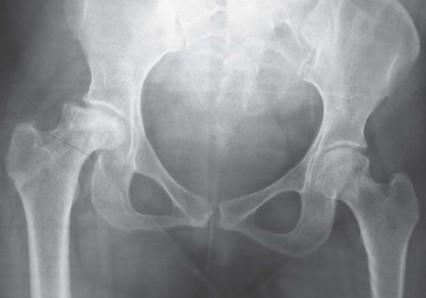

التصوير الإشعاعي

تُعد الأشعة السينية (X-rays) الأداة التشخيصية الأساسية لتصوير مفصل الفخذ. يُطلب عادة:

* صورة شعاعية أمامية خلفية (AP) للحوض مع كلا مفصلي الفخذ: هذه الصورة تسمح بتقييم شامل لكلا المفصلين، وتحديد مركز رأس الفخذ، وطول الساق، والإزاحة (offset)، ومستوى قطع عنق الفخذ المحتمل، وحجم الجذع.

* صورة شعاعية جانبية للمفصل المصاب مع تكبير 15%: لتوفير رؤية إضافية لهيكل المفصل وتخطيط الزرع.

التخطيط قبل الجراحة

يُعد التخطيط الدقيق قبل الجراحة أمرًا بالغ الأهمية لنجاح جراحة METHA قصير الجذع. يتضمن ذلك استخدام قوالب خاصة على الأشعة السينية لـ:

* تحديد حجم الزرعة: اختيار الحجم المناسب للجذع والمكون الحُقي.

* تخطيط قطع عنق الفخذ: يجب أن يكون القطع بزاوية 50 درجة بالنسبة للمحور الطولي لعظم الفخذ، مع الحفاظ على 5-10 ملم من القشرة الجانبية لعنق الفخذ.

* استعادة ميكانيكا المفصل: ضمان استعادة مركز رأس الفخذ، وطول الساق، والإزاحة إلى الوضع الفسيولوجي الطبيعي.

* تحديد زاوية عنق الفخذ: تُقاس زاوية عنق الفخذ في الجانب غير المصاب إن أمكن، لمساعدة الجراح في اختيار محول العنق المناسب أثناء الجراحة.

تساعد هذه الخطوات الدقيقة في ضمان اختيار الزرعة المناسبة وتحديد موضعها الأمثل، مما يقلل من مخاطر المضاعفات ويحسن النتائج الوظيفية للمريض. يتمتع الأستاذ الدكتور محمد هطيف في صنعاء بخبرة واسعة في التخطيط الدقيق وتنفيذ هذه الجراحات المعقدة، مستخدمًا أحدث التقنيات لضمان أفضل النتائج لمرضاه.